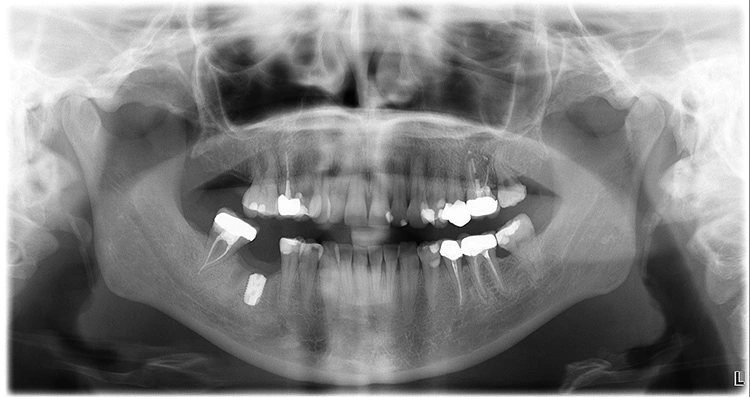

Die Dokumentation des Implantatsitzes erfolgte mit einer postoperativen Panoramaschichtaufnahme (Abb. 16). Nach der gedeckten Einheilung erfolgte im Juni 2021 die geschlossene Implantatabformung mit Impregum. Abbildung 17 bis 25 zeigt den Ablauf von der Inzision drei Monate nach Implantation bis zum Einsetzen des Hybrid-Abutments mit Titan-Klebebasis und Zirkonaufbau bis zur finalen Zirkonkrone, die aufgrund einer Erkrankung der Patientin etwas später als vorgesehen im Juli 2021 eingegliedert werden konnte. Die Versorgung der insuffizienten Einzelkrone 47 erfolgt auf Patientenwunsch zu einem späteren Zeitpunkt.